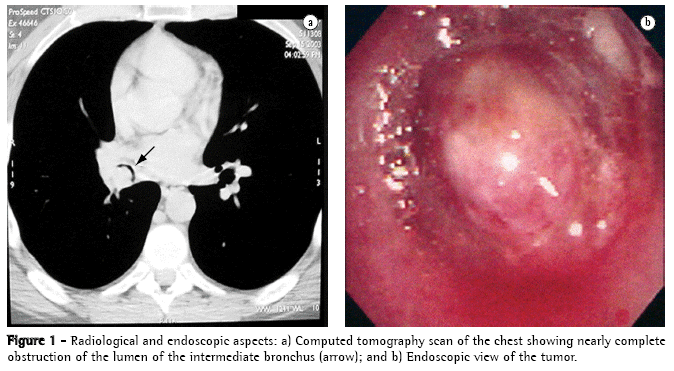

A 36-year-old male nonsmoker was admitted for investigation of chronic cough and wheezing. Physical examination revealed right-sided expiratory wheezing. A simple chest X-ray revealed atelectasis of the right lower lobe, and a tomography scan of the chest revealed an endobronchial mass (Figure 1a). Bronchoscopy identified a vegetative lesion that completely obstructed the intermediate bronchus (Figure 1b), and the biopsy findings were suggestive of hemangioma. The patient was systematically staged due to the hypothesis of it being bronchial neoplasia. Since there was no evidence of local, regional, or remote impairment, the patient underwent a right lateral thoracotomy for resection of the lower lobe. Due to the extent of the endobronchial involvement, with impairment of the intermediate bronchus but without invasion of the middle lobe bronchus, we decided to perform a lower lobectomy with partial resection of the intermediate bronchus and reconstruction, including the creation of an anastomosis between the proximal part of the intermediate bronchus and the middle lobe bronchus. The postoperative evolution was favorable and uneventful. The patient was discharged on postoperative day 5. The tumor originated in the apical segmental bronchus of the right lower lobe (Figure 2). The anatomical and pathological diagnosis was that of inflammatory fibrohistiocytic pseudotumor (Figure 3), which was confirmed through immunohistochemistry.